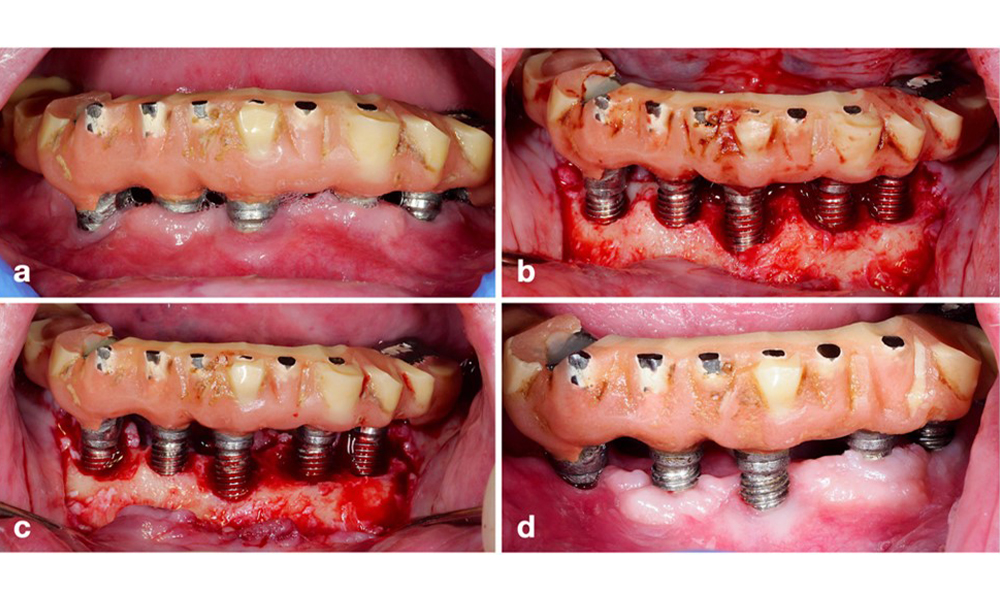

Since the primary etiologic factor for peri-implant biological complications is the oral biofilm, two crucial aspects should always be considered as integral part of the treatment independent of a diagnosis of peri-implant mucositis or peri-implantitis: (1) the level of oral hygiene, and (2) the cleanability of the prosthetic restoration (figure 4).

Lower jaw full-arch restoration with significant plaque accumulation due to poor oral hygiene. Notice the large distance of the buccal aspect of the prosthesis to the implants on the right side (white arrows).

Figure 4. Lower jaw full-arch restoration with significant plaque accumulation due to poor oral hygiene. Notice the large distance of the buccal aspect of the prosthesis to the implants on the right side (white arrows).

Thus, both the patient's oral hygiene routines and the prosthetic restoration’s design and implant positioning should support effective cleaning. If required, adjustments to the existing restoration (figure 5) and specific instructions for tailored oral hygiene measures are essential (figure 6) (Hamilton et al. 2023; Jepsen et al. 2015).

Modification of an existing bridge restoration. If the restoration hinders sufficient oral hygiene measures (notice the extreme overhang on the buccal aspect of the molar) (a–b), one of the first treatment steps should be adjusting the prosthetic design to enable effective cleaning (c–d).

Figure 5. Modification of an existing bridge restoration. If the restoration hinders sufficient oral hygiene measures (notice the extreme overhang on the buccal aspect of the molar) (a–b), one of the first treatment steps should be adjusting the prosthetic design to enable effective cleaning (c–d).